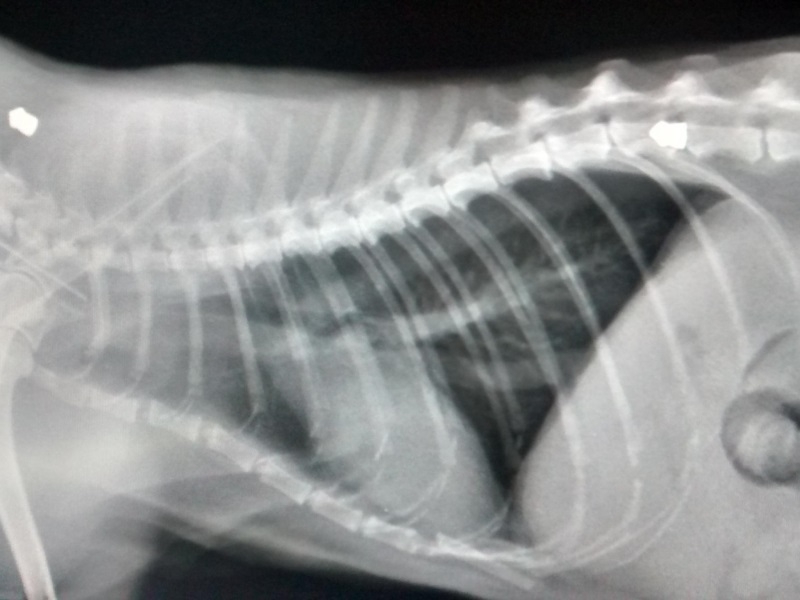

- Переломы, травмы, ушибы. Неудачное падение, драки с другими особями, попадание в ДТП приводят к различным травмам позвоночного столба. Если животное пострадало в подобных ситуациях, требуется незамедлительное обращение в клинику. Проведение рентгена позволит определить место перелома. Оперативная помощь поможет восстановить активность кошки в короткие сроки. Даже маленькая рана, полученная во время драки с котами может привести к сильной болезненности. Животное будет мучиться от дискомфорта, боли, невозможности совершать маневры во время прыжков, неудобство во время сна (котам требуется принимать наиболее безопасную позу для отдыха, поджимая хвост, а если он болит, то питомец длительное время не может устроиться для сна);

Вовремя оказанная первая помощь любимцу может спасти ему жизнь. При переломе следует поместить кота в состояние покоя и путем аккуратной транспортировки в переноске отвезти к ветврачу. После осмотра делается рентген и выписываются нужные лекарства. В некоторых случаях накладывается гипс.

1) Заболевание позвоночника. Рентген./rn/

Для точной диагностики желательно провести компьютерную томографию, MRI (магнитно-резонансную томографию), а также (или хотя бы) рентгенографию позвоночного столба. Обязательно берется проба спинального ликвора (посредством пункции), так как анализ этой жидкости с высокой степенью достоверности позволяет выявлять различные виды воспалительных и инфекционных патологий.